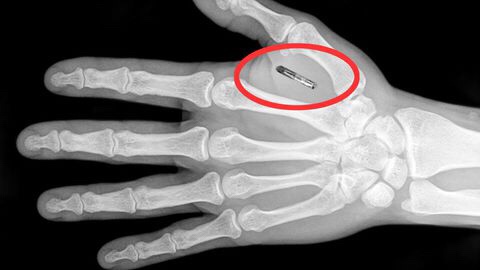

Il portafoglio non è il massimo della comodità: se lo perdiamo, o ci viene rubato, ci ritroviamo all’improvviso senza contanti, senza documenti e senza carte di credito. E che dire delle chiavi di casa? Accorgersi davanti al portone di averle smarrite può essere davvero un casino. Da questo punto di vista, le nuove tecnologie che permettono di pagare o di aprire la porta di casa usando lo smartphone non sono un grande passo avanti; perché perderlo – o peggio scoprire che è stato hackerato – sarebbe una tragedia.